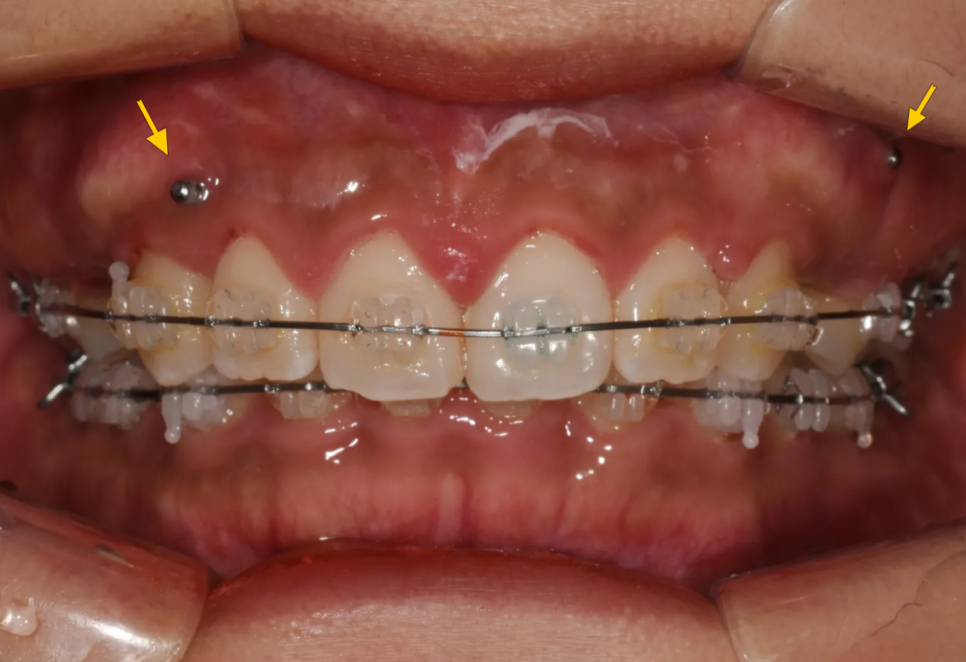

치료 시작: 장치 부착과 스크류 식립

치료 초반부터 적극적으로 미니스크류를 식립하여 앞니 상방이동을 시작했습니다. 동시에 환자분이 원하셨던 요구사항('앞니의 존재감을 줄이고 싶다')을 달성하기 위해 위쪽 작은어금니 발치를 진행했습니다. 앞니 후방이동량을 극대화 할 수 있으니까요.

스크류(노랑) 식립 및 작은어금니 발치 후 치료 시작 모습

측면 모습. 발치한 공간으로 위쪽 앞니들을 당겨 넣게 됩니다.

위·아래 모두 교정 장치(브라켓)를 부착하고, 치열궁 확장과 과개교합 개선을 동시에 진행했습니다. 여러 가지 문제를 한꺼번에 효율적으로 해결하기 위한 전략이었습니다.